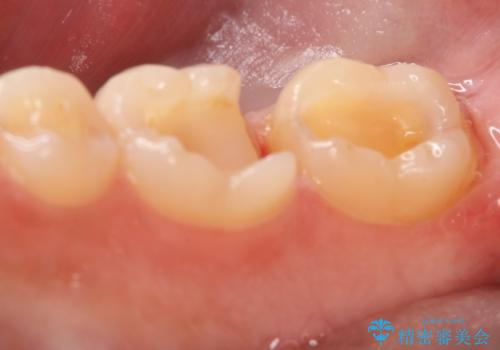

- 右下6・7番の治療のやり変えを主訴に来院された患者様です。

保険の材料が劣化し中で虫歯が進行しているため、古い材料と虫歯を全て除去した上で詰め直す必要がありました。

切削量・形態を考慮し、セラミックインレーでの治療を計画しました。